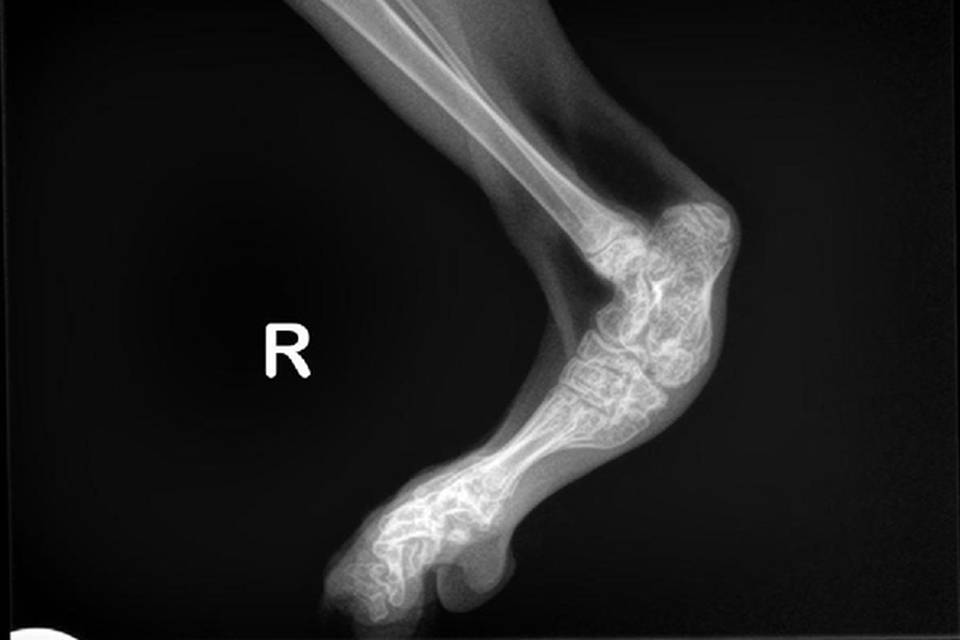

SFO is een erfelijke aandoening die voorkomt bij de Scottish Fold. Door deze afwijking zal het kraakbeen niet normaal volgroeien en functioneren. Hierdoor ontstaat ernstige artrose. Dit kan al op jonge leeftijd zichtbaar zijn en leidt ertoe dat aangetaste dieren mank en stijf gaan lopen en minder of niet willen springen.

De diagnose kan bevestigd worden door het maken van röntgenfoto's.